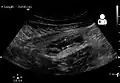

Abdominal ultrasonography, preferably with doppler sonography, is useful to detect appendicitis, especially in children. Ultrasound can show the free fluid collection in the right iliac fossa, along with a visible appendix with increased blood flow when using color Doppler, and noncompressibility of the appendix, as it is essentially a walled-off abscess. Other secondary sonographic signs of acute appendicitis include the presence of echogenic mesenteric fat surrounding the appendix and the acoustic shadowing of an appendicolith.[59] In some cases (approximately 5%),[60] ultrasonography of the iliac fossa does not reveal any abnormalities despite the presence of appendicitis. This false-negative finding is especially true of early appendicitis before the appendix has become significantly distended. Also, false-negative findings are more common in adults where larger amounts of fat and bowel gas make visualizing the appendix technically difficult. Despite these limitations, sonographic imaging with experienced hands can often distinguish between appendicitis and other diseases with similar symptoms. Some of these conditions include inflammation of lymph nodes near the appendix or pain originating from other pelvic organs such as the ovaries or Fallopian tubes. Ultrasounds may be either done by the radiology department or by the emergency physician.[61]

Ultrasound showing appendicitis and an appendicolith.[62]

Ultrasound showing appendicitis and an appendicolith.[62] -

A normal appendix without and with compression. Absence of compressibility indicates appendicitis.[59]